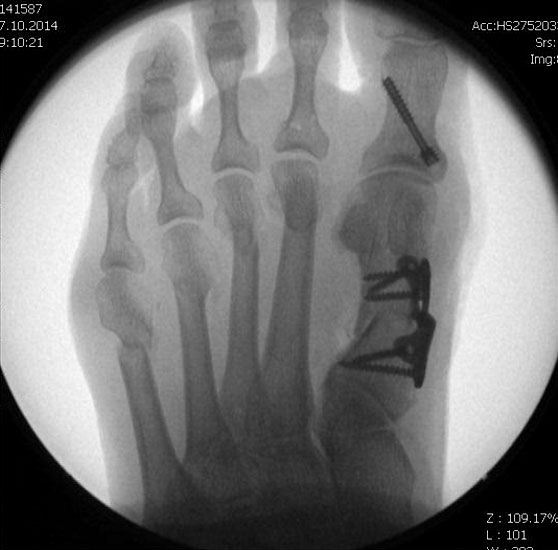

Die Stichinzisionen können genäht, aber auch nur mit Steristrips verschlossen werden. Im Anschluss erfolgt die Anlage eines sterilen Verbandes unter Miteinbeziehung der Zehenzwischenräume, mit einer leichten Kompression im Bereich der Metatarsalia durch eine Kohäsivbinde wie z.B. Coban®. So kann das Alignement gesichert werden. Sollten die DMMO´s als alleinige Maßnahme durchgeführt worden sein, kann der Patient direkt postoperativ in einem post-OP Schuh mit steifer Abrollsohle voll belasten. Der Patient muss darüber informiert sein, dass auch nach Entfernung des Wundverbandes die Elastokompressivverbände im Metatarsalebereich bis Abschluss der 6.postOP Woche regelmäßig anzulegen sind. Die Anlagetechnik sollte mit dem Patienten bereits präoperativ geübt werden. Bei Patienten mit geringer Compliance ist die Indikation für eine DMMO mit der Notwendigkeit eines über mehrere Wochen lückenlos zu tragenden Elastokompressivverbandes kritisch zu prüfen; engmaschigere Nachkontrollen als bei offener Vorgehensweise sind bis Ende der 6.post OP Woche nötig.

Postoperative Behandlung

• Bei DMMO als isoliertem OP-Verfahren schmerzadaptierte Belastung im post-OP Schuh sofort möglich, bei zusätzlichen Eingriffen im Fußbereich Belastung in Abhängigkeit von diesen

• Röntgenkontrolle nach 14 Tagen und nach 6 Wochen